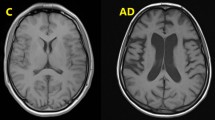

Previous studies have reported the presence of mtDNA in human saliva [12,13,14,15,16,17,18], but its relationship with AD biomarkers has remained unexplored so far. Here, we showed that higher levels of salivary mtDNA were associated with greater Aβ burden in occipital regions, higher plasma pTau-181 levels, and lower cognitive ability in cognitively normal older adults. Remarkably, plasma pTau-181 levels moderated the association between salivary mtDNA and Aβ accumulation in regions of the inferior temporal lobe. In contrast, the relationship between salivary mtDNA and plasma pTau-181 was mediated by Aβ accumulation in occipital regions. Together, these results provide new evidence linking salivary mtDNA to well-established AD biomarkers, highlighting associations between salivary mtDNA and AD pathology before the onset of clinical symptoms.